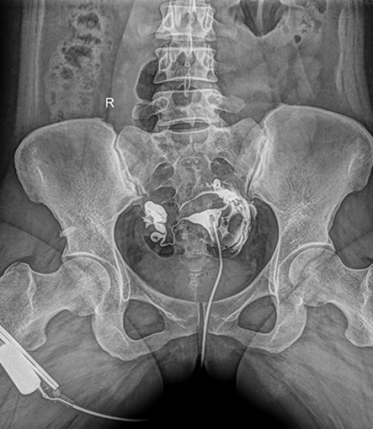

多功能動(dòng)態(tài)平板DR,采用U型臂結(jié)構(gòu),具有靜態(tài)DR攝影、數(shù)字透視、數(shù)字造影和可視化攝影的功能。

● 配備智能化電動(dòng)床體,可隔室電動(dòng)控制,減少醫(yī)生與患者的直接接,避免交叉感染。

● 在臥床大范圍檢查時(shí),無(wú)需近臺(tái)操作。